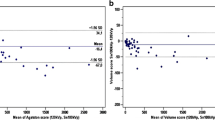

Overall, there was a very good correlation between scores calculated with 120 and 80 kVp tube voltage scans (R = 0.94, R2 = 0.88, P > .001). Bland–Altman limits of agreement of − 563.5 to 871.9 and a bias of − 154.2 (Figures 1, 2).

There was a difference between the proportion of patients assigned in the < 25% percentile class (P = .03) (25.0% in standard CT acquisition vs 39.1% in low-dose CT acquisition). Conversely, the proportion of patients assigned to the percentile classes other than < 25% did not differ between the two acquisition protocols. The results are summarized in Table 2 and in Figure 3.

Moreover, we found a significant difference in the proportion of patients with CACS = 0 between standard acquisition (n = 264, 17.5%) and low-dose scan (n = 437, 28.9%, P < .001). The 437 patients with CACS = 0 with the low-dose scan had CACS ranging between 0 and 372 (median 0, IQR 0 to 4). Among patients with CACS = 0 in the low-dose imaging, 173 had CACS > 0 on the standard acquisition. Of note, these 173 patients are mostly coming from the < 25% risk class as assessed with the standard protocol. In only 9/173 Patients (5%) the standard acquisition showed markedly higher values (i.e., from the 25% to 50% risk class, median 6, IQR 1 to 3).

However, the impact on the diagnosis (normal vs abnormal) and on the prognostic value should be further discussed. In fact, if a low-dose CCT is used, significantly more patients are considered as not having any coronary calcifications, and this may lead to an underestimation of the cardiovascular risk in these patients. In our patients’ population, 173 Patients (11.6%) were falsely diagnosed as non-CAD due to CACS = 0 with the low-dose protocol, but > 0 with the standard protocol (median 6, IQR 1 to 3). Of note, all patients with CACS = 0 with the standard protocol also had CACS = 0 with low-dose protocol. A low calcium score is still consistent with a favorable prognosis, with the exception of very young patients, as the majority of events occur in individuals with high CACS percentile classes.8 As such, consistent with data from the literature, CACS percentile classes may constitute an effective screening method to stratify individuals at risk as well, and in this regard, our data showed a very good correlation across percentiles classes (r = 0.857, r2 = 0.74, P < .001). But as a matter of fact, the power of zero22 and its ability to predict a long disease-free survival in patients with suspected CAD22 should be considered reliable only if the CACS is assessed by standard protocols. This latter aspect has an evident impact in clinical practice, wherein patients are normally referred to calcium scoring as primary prevention if asymptomatic. In such patients, a precise diagnosis of CAD is essential to plan an adequate primary prevention. The same does not hold true for a patients’ population similar to that of the present study, wherein patients were referred to an ischemia test in view of their high cardiovascular risk and/or symptoms. While a standard protocol is mandatory if CACS is calculated as standalone modality, the same may not hold true if an ischemia test such as MPS is associated. In this latter setting, the implementation of low-dose protocols for the calculation of CACS may be pursued without relevant loss in prognostic power. Thus, low radiation dose protocols might be used without relevant impairment in accuracy, thus maintaining a reliable risk stratification for medical therapy.